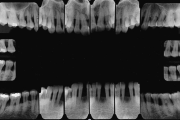

Krooniline parodontiit on mikroobide poolt põhjustatud hammaste tugikudede põletik, mille tulemusena tekib progresseeruv alveolaarluu (nähtav röntgenograamil) ja periodontaalligamendi destruktsioon, igemetaskute moodustumine, igeme retsessioon või mõlemad kahjustused kombineeritult. Loe edasi »

- luu destruktsioon (5)

- vertikaalne luukadu (2)

- horisontaalne luukadu (3)